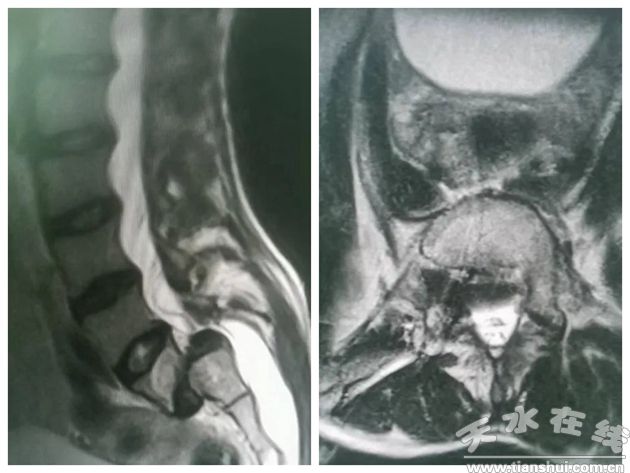

該患者為18歲男性,因腰部疼痛不適3年,加重伴左側(cè)下肢麻木3月,最遠(yuǎn)行走約200m,腰部VAS8;左下肢VAS3。曾輾轉(zhuǎn)于多家醫(yī)院治療,未有明顯改善,給患者帶來了巨大的痛苦,嚴(yán)重影響生活質(zhì)量。

由于患者年齡小,整體椎弓根發(fā)育細(xì)小,入院后組織多學(xué)科病例討論,麻醉科和手術(shù)室團(tuán)隊的全力配合,骨科團(tuán)隊歷時5小時的全力奮戰(zhàn),成功為患者精確置入椎弓根螺釘及S2AI螺釘,將滑脫椎體基本完全復(fù)位,重建了患者全脊柱序列。手術(shù)后腰部VAS 2分;左下肢VAS 0分,患者訴左下肢疼痛明顯減輕,肢體功能逐漸恢復(fù),現(xiàn)在已經(jīng)可以在胸腰椎治具的幫助下進(jìn)行下床負(fù)重行走。